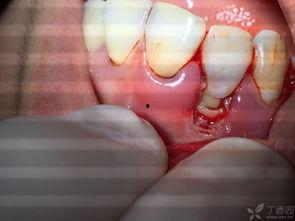

牙龈烂了,图片告诉你真相

来看看这些牙龈烂了的图片,是不是觉得有点吓人?红肿的牙龈,甚至可以看到一些小洞洞,这就是牙龈炎的典型表现。如果你发现自己也有类似的情况,那可要赶紧重视起来了!